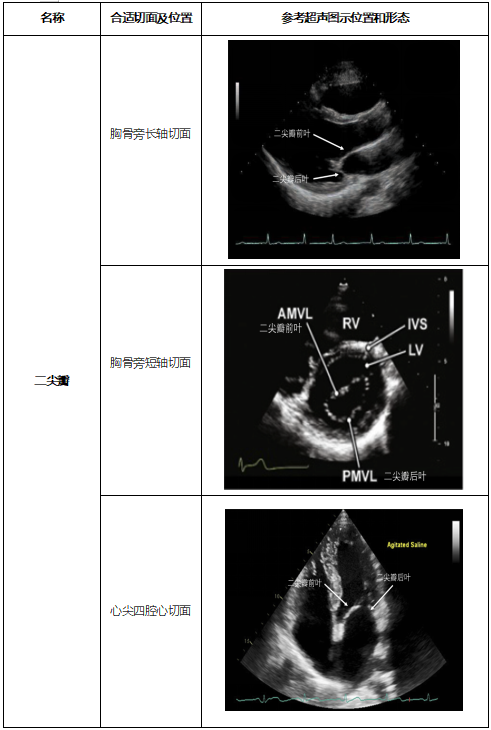

1.2  心脏各瓣膜形态观察、评估

我们在超声下可以观察到的主要心脏瓣膜包括二尖瓣、三尖瓣、主动脉瓣、肺动脉瓣,合适的超声观察位置和形态如表2推荐。

表2  心脏瓣膜合适的超声观察位置和形态

图片